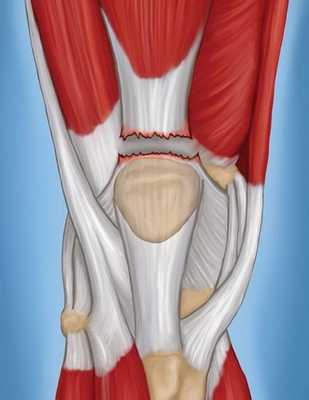

Четырехглавая мышца бедра состоит из четырех отдельных мышц, сухожилия которых объединяются тотчас выше надколенника и образуют единое сухожилие, прикрепляющееся к верхнему полюсу надколенника. Надколенник соединяется с большеберцовой костью посредством сухожилия надколенника. Четырехглавая мышца, ее сухожилие, надколенник и сухожилие надколенника вместе образуют разгибательный механизм коленного сустава.

Сухожилия в области коленного сустава. С помощью сухожилий мышцы прикрепляются к костям.

Полный разрыв сухожилия четырехглавой мышцы.